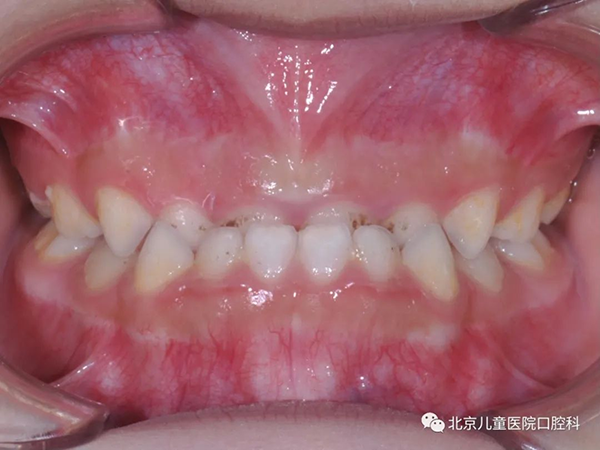

反牙合,也就是我们俗称的“地包天”,这是一种常见的咬合问题。那什么叫“地包天”呢?简单地说,就是当孩子后牙咬住的时候,下牙在上牙的外面。“地包天”不仅影响牙齿健康和颌骨发育,还会影响孩子吃东西、说话等方面的口腔功能,同时还严重影响孩子的面部美观,因此使得“地包天”成为如今最受家长关注的口腔问题之一。那么,孩子的牙齿为什么会形成“地包天”呢?